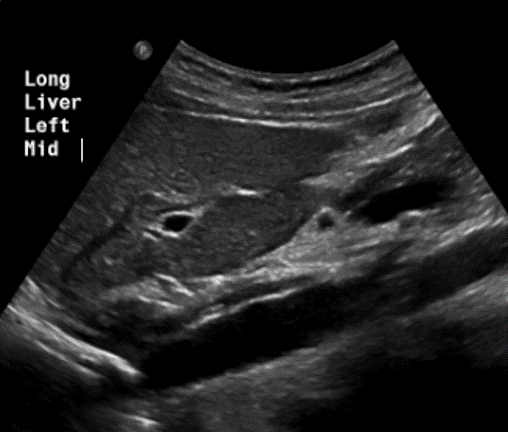

<p>In this sagittal view, what is the structure in this image?</p>

In this sagittal view, what is the structure in this image?

Celiac Trunk